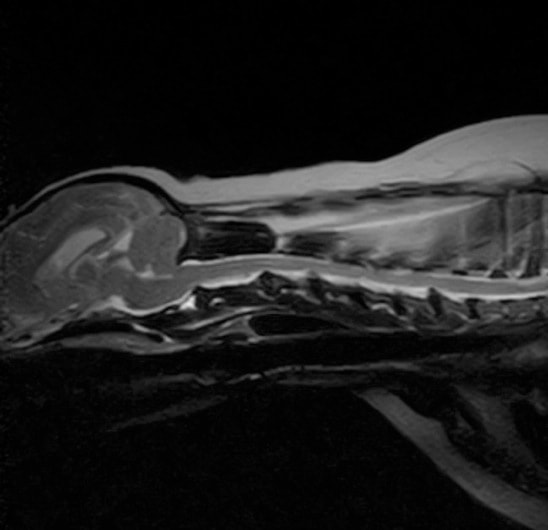

■ MRI検査

第5-6腰椎間で右側神経根が腫大し、脊柱管内に連続した腫瘤病変が認められました。脊髄および馬尾神経は右側から重度に圧迫されていました。

MRI検査所見

MRI 2